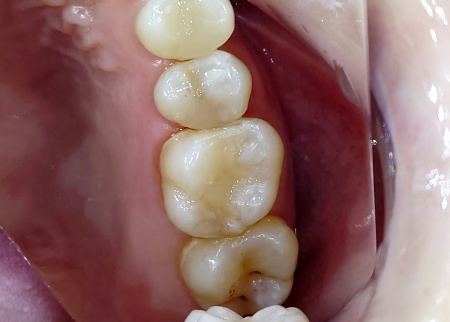

治療中

虫歯治療後に行う修復方法について、以下の提案を行いました。 ①保険診療で修復 ②自費診療で修復 患者様はそれぞれメリットとデメリットをしっかりご理解いただいたうえで、②の自費診療での治療を選択されました。 まず、取り残しがないようにしっかりと虫歯を除去し、歯の形を整えてから型取りを行いました。 後日、完成したE-MAXインレーを装着し、噛み合わせや見た目に問題がないことを確認して、治療を終了しました。 |